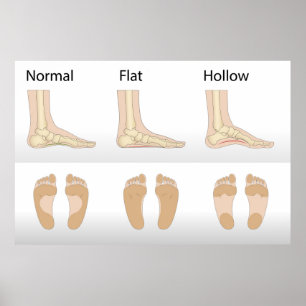

Struktur des menschlichen Fußes Poster

PreisCHF 85.40